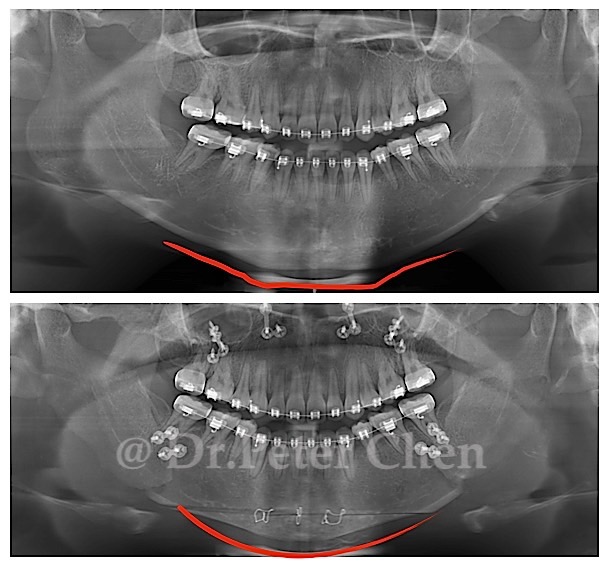

有些下顎骨突出的案例,從 X ray 上 會發現下顎骨前端(Menton)特別會突出一塊,

不笑時因軟組織包住較不明顯,笑的時候因為軟組織變薄了,骨骼的形狀就顯現出來,讓人有下巴多了一塊骨頭的錯覺。

在手術設計上,除了利用正顎手術將下顎骨退後,最好同時將下顎骨前端的骨骼重新雕塑,才能達到理想的效果。